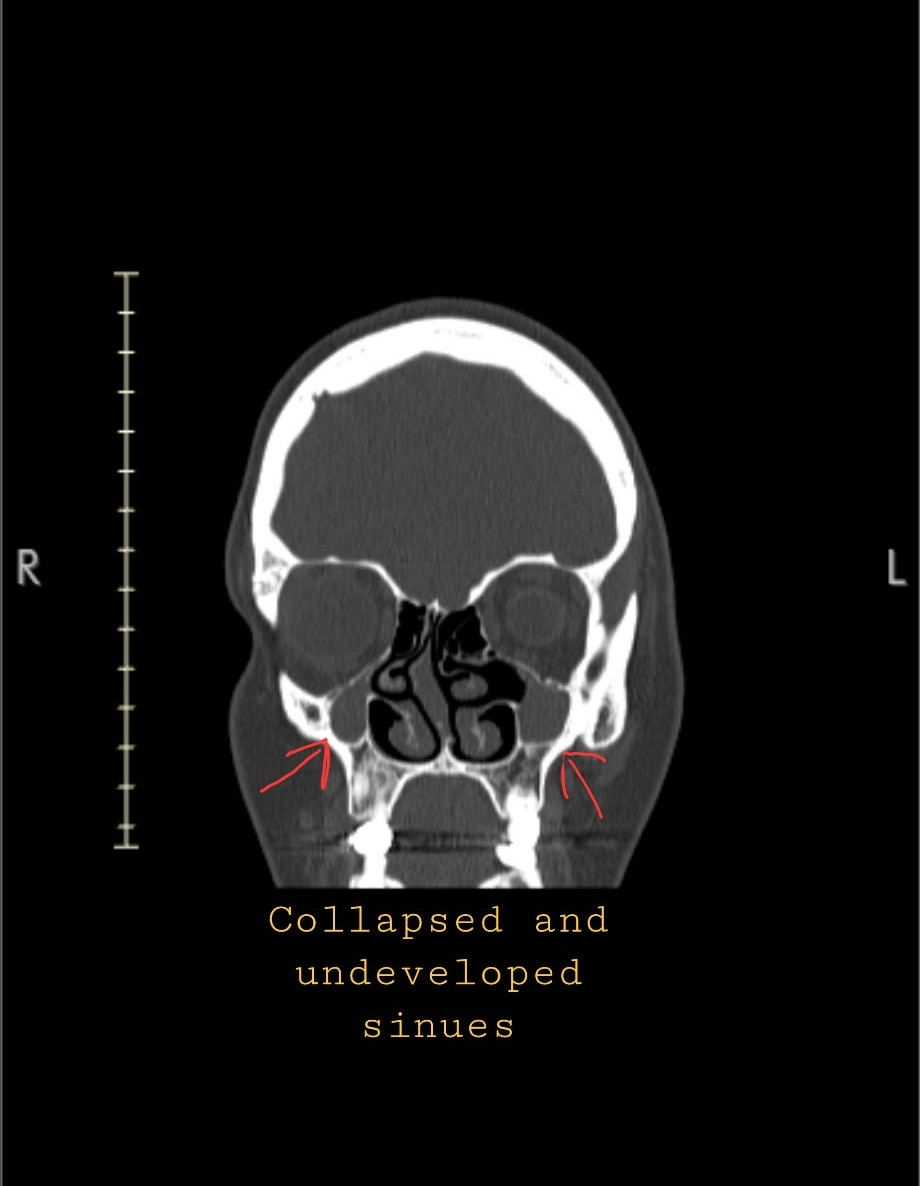

Hi, I’m Jenna. I’m preparing for major nasal and sinus surgery to fix something I’ve been quietly dealing with my entire life. I was born prematurely, weighing just 2 pounds and a few ounces, and my sinuses didn’t fully develop as they should have. Then between the ages of 4 and 6, I broke my nose three times — injuries that were never corrected.

Now at 25, I’m facing the long-term effects: a broken nose, a completely deviated septum, and collapsed sinuses that make it hard to breathe, sleep, or live comfortably day to day.

Repairing my collapsed sinuses